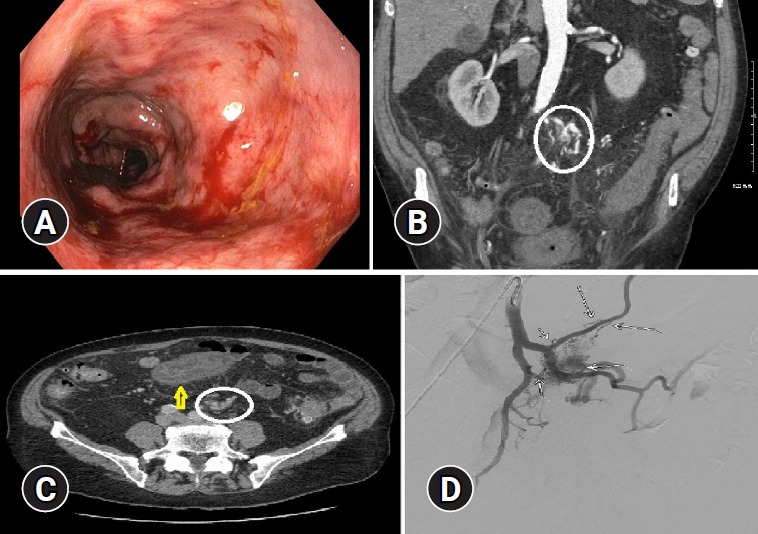

肠系膜动静脉畸形伴肠系膜下静脉闭塞:缺血性结肠炎的罕见病因。

Mesenteric arteriovenous malformation with associated inferior mesenteric vein occlusion: a rare cause of ischemic colitis.